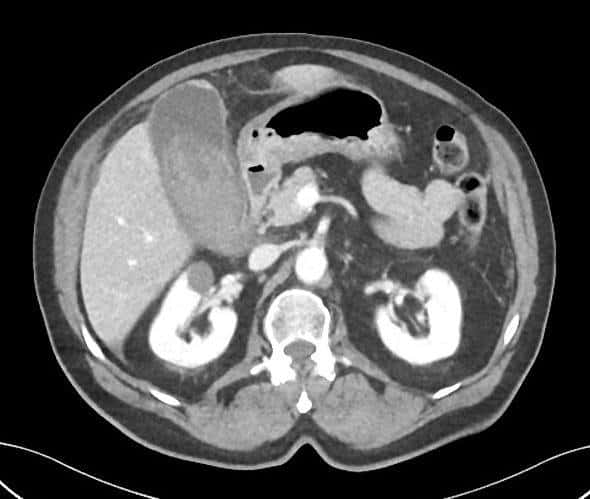

Vỡ túi mật

» Thông tin: Nam giới – 80 tuổi.

» Lâm sàng: Chấn thương.